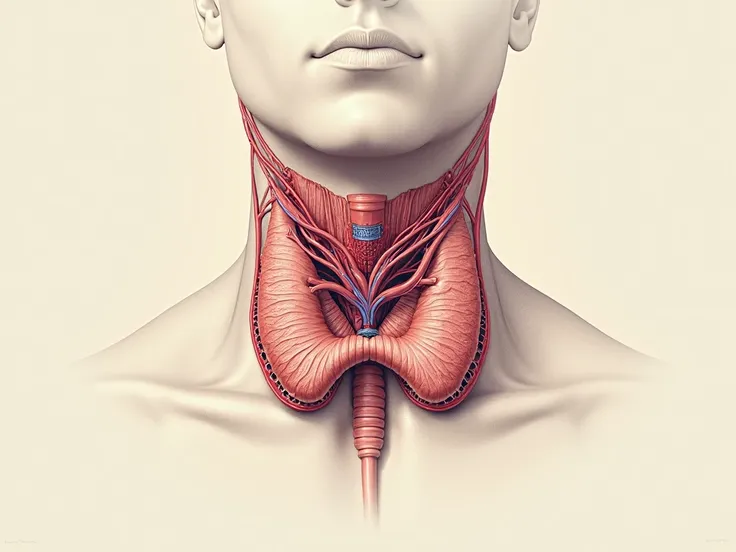

Pictures of swollen thyroid gland in neck, Use a Canon EOS 5D Mark IV with a 24

pictures of swollen thyroid gland in neck, Use a Canon EOS 5D Mark IV with a 24-70mm f/2.8 lens. Settings: ISO 100, aperture f/8, and shutter speed 1/125s to capture a sharp, vibrant image with a wide depth of field.

pictures of swollen thyroid gland in neck